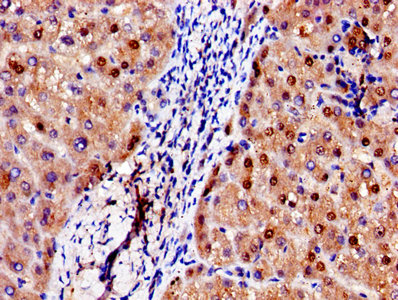

Immunohistochemistry of paraffin-embedded human heart tissue using CSB-PA001311LA01HU at dilution of 1:100

Immunohistochemistry of paraffin-embedded human liver tissue using CSB-PA001311LA01HU at dilution of 1:100

IHC image of CSB-PA001311LA01HU diluted at 1:250 and staining in paraffin-embedded human lung tissue performed on a Leica BondTM system. After dewaxing and hydration, antigen retrieval was mediated by high pressure in a citrate buffer (pH 6.0). Section was blocked with 10% normal goat serum 30min at RT. Then primary antibody (1% BSA) was incubated at 4°C overnight. The primary is detected by a biotinylated secondary antibody and visualized using an HRP conjugated SP system.